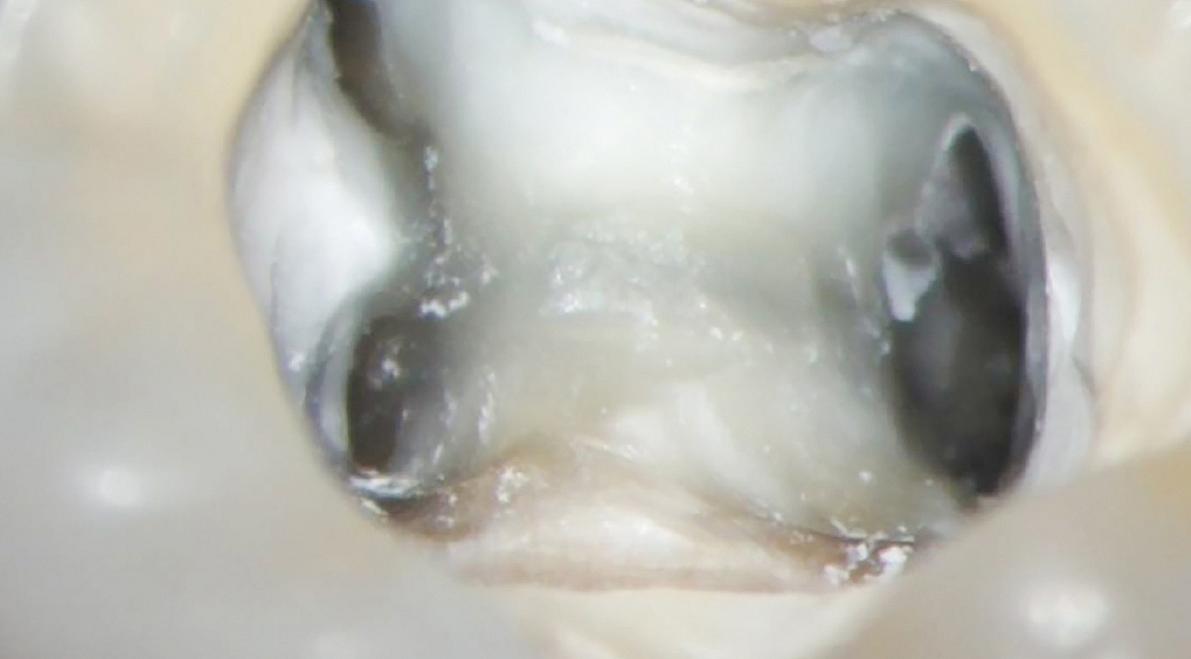

- kunt u de betekenis aangeven van de verschillende dentinekleuren die op de bodem van de pulpakamer te zien zijn

- kent u verschijnselen die op extra wortelkanalen duiden, zoals de witte en rode lijntjes en cirkeltjes op de bodem van de pulpakamer en opstijgende gasbelletjes